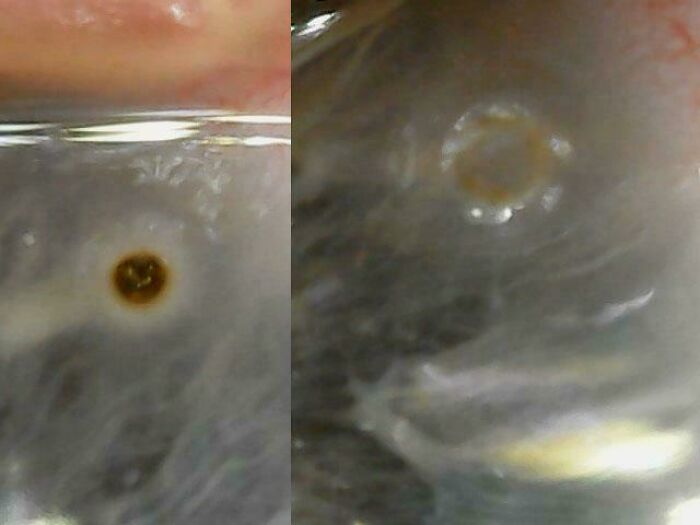

Metal Chunk Got Lodged In My Eyeball While Grinding And Wearing A Face Shield. Ouch